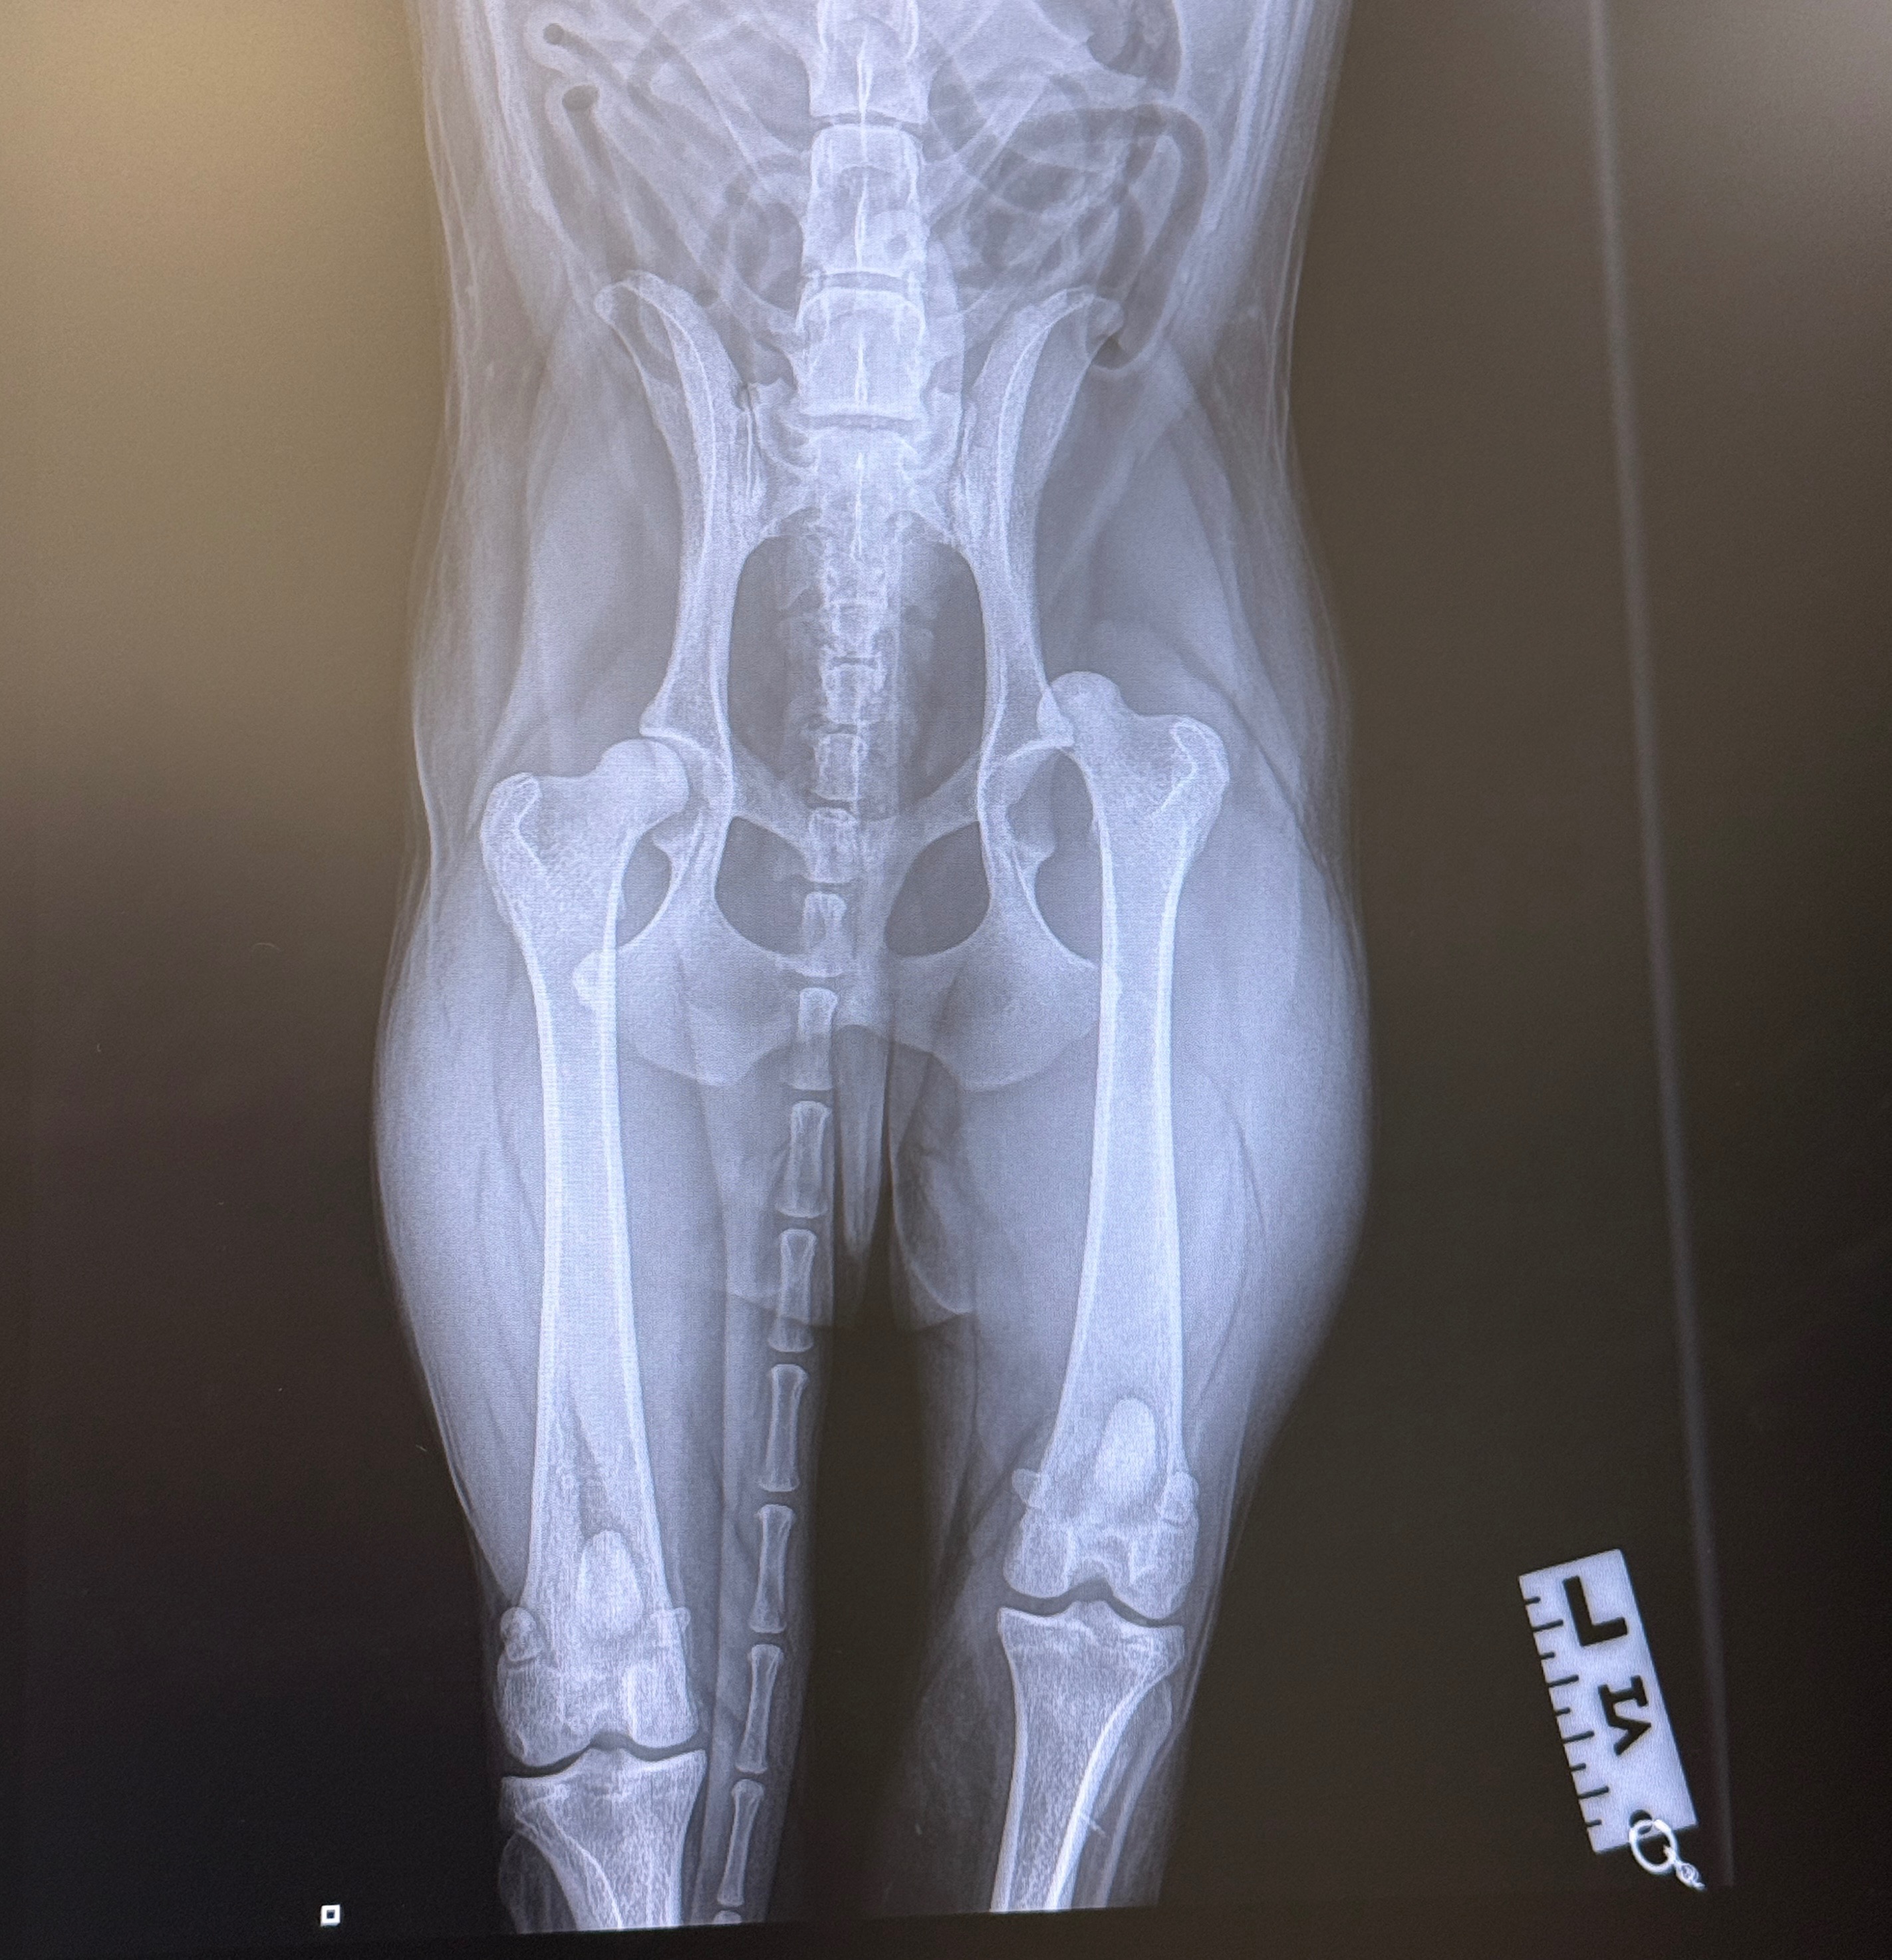

I’m raising funds to help my dog Milo who is a rescue who has recently suffered a serious hip injury. He has been diagnosed with a dislocated hip, and after attempts to put it back into place were unsuccessful, surgery is now the only option to get him out of pain and walking properly again.